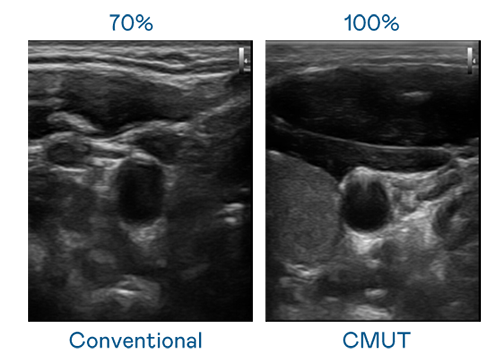

CMUT 技术是一种用电容式微机电元件来产生超音波讯号的技术。与传统 PZT 压电式技术相比,CMUT 频宽增加 30%,更宽频的超音波讯号让影像解析度大幅提升,是实现高影像品质医疗超音波扫描、促进精准医疗发展的关键技术。

大频宽带来超清晰影像

超音波影像的解析度高低,首先取决于探头能发出的讯号频宽。AB娱乐 CMUT 可提供高清晰的超音波讯号,提供高频宽、高灵敏度、影像纹理细节更高的超音波影像,协助医护人员缩短影像判读时间及利用精准的医疗影像进行诊断。